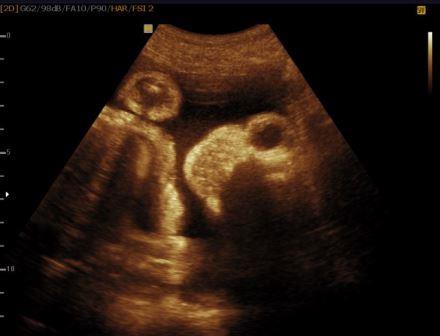

La diagnosi ecografica è relativamente semplice. A 11-12 settimane la volta cranica è assente mentre gli emisferi cerebrali sono ancora riconoscibili e circondati da una sottile membrana a diretto contatto con il liquido amniotico ( acrania-exencefalia ). In sezione coronale l'estremo cefalico assume un aspetto "a mickey mouse"determinato dalla visualizzazione degli emisferi cerebrali come due strutture semicircolari al disopra delle orbite.

In sezione coronale, per la presenza di macroftalmia, l'estremo cefalico assume il tipico aspetto "a rana".